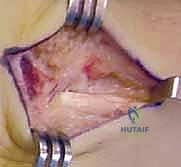

Here, we observe a classic presentation of a failed open reduction and internal fixation (ORIF) of a scaphoid nonunion. Despite surgical intervention, the biological and mechanical environment was insufficient to achieve osteosynthesis, leading to hardware failure and persistent nonunion.

Figure 1A: Failed ORIF of a scaphoid nonunion (PA view) demonstrating hardware loosening and persistent radiolucency at the fracture site.

The Volar Approach and Deep Dissection

An 8-cm longitudinal or slightly curvilinear incision is made over the volar aspect of the wrist, centered over the Flexor Carpi Radialis (FCR) tendon, extending from the distal wrist crease proximally.